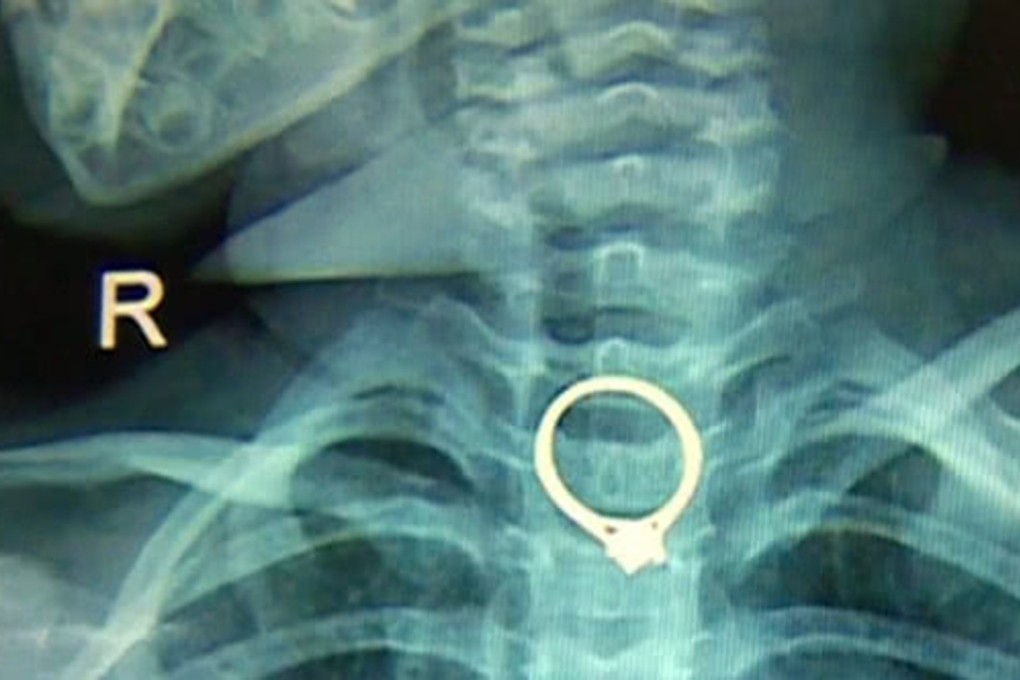

Two-year-old Chinese girl swallows mother’s diamond ring

Child has to undergo surgery to remove jewellery that became stuck in her throat

A two-year-old girl in southern China accidentally swallowed her mother’s diamond ring while playing with it, local television has reported.